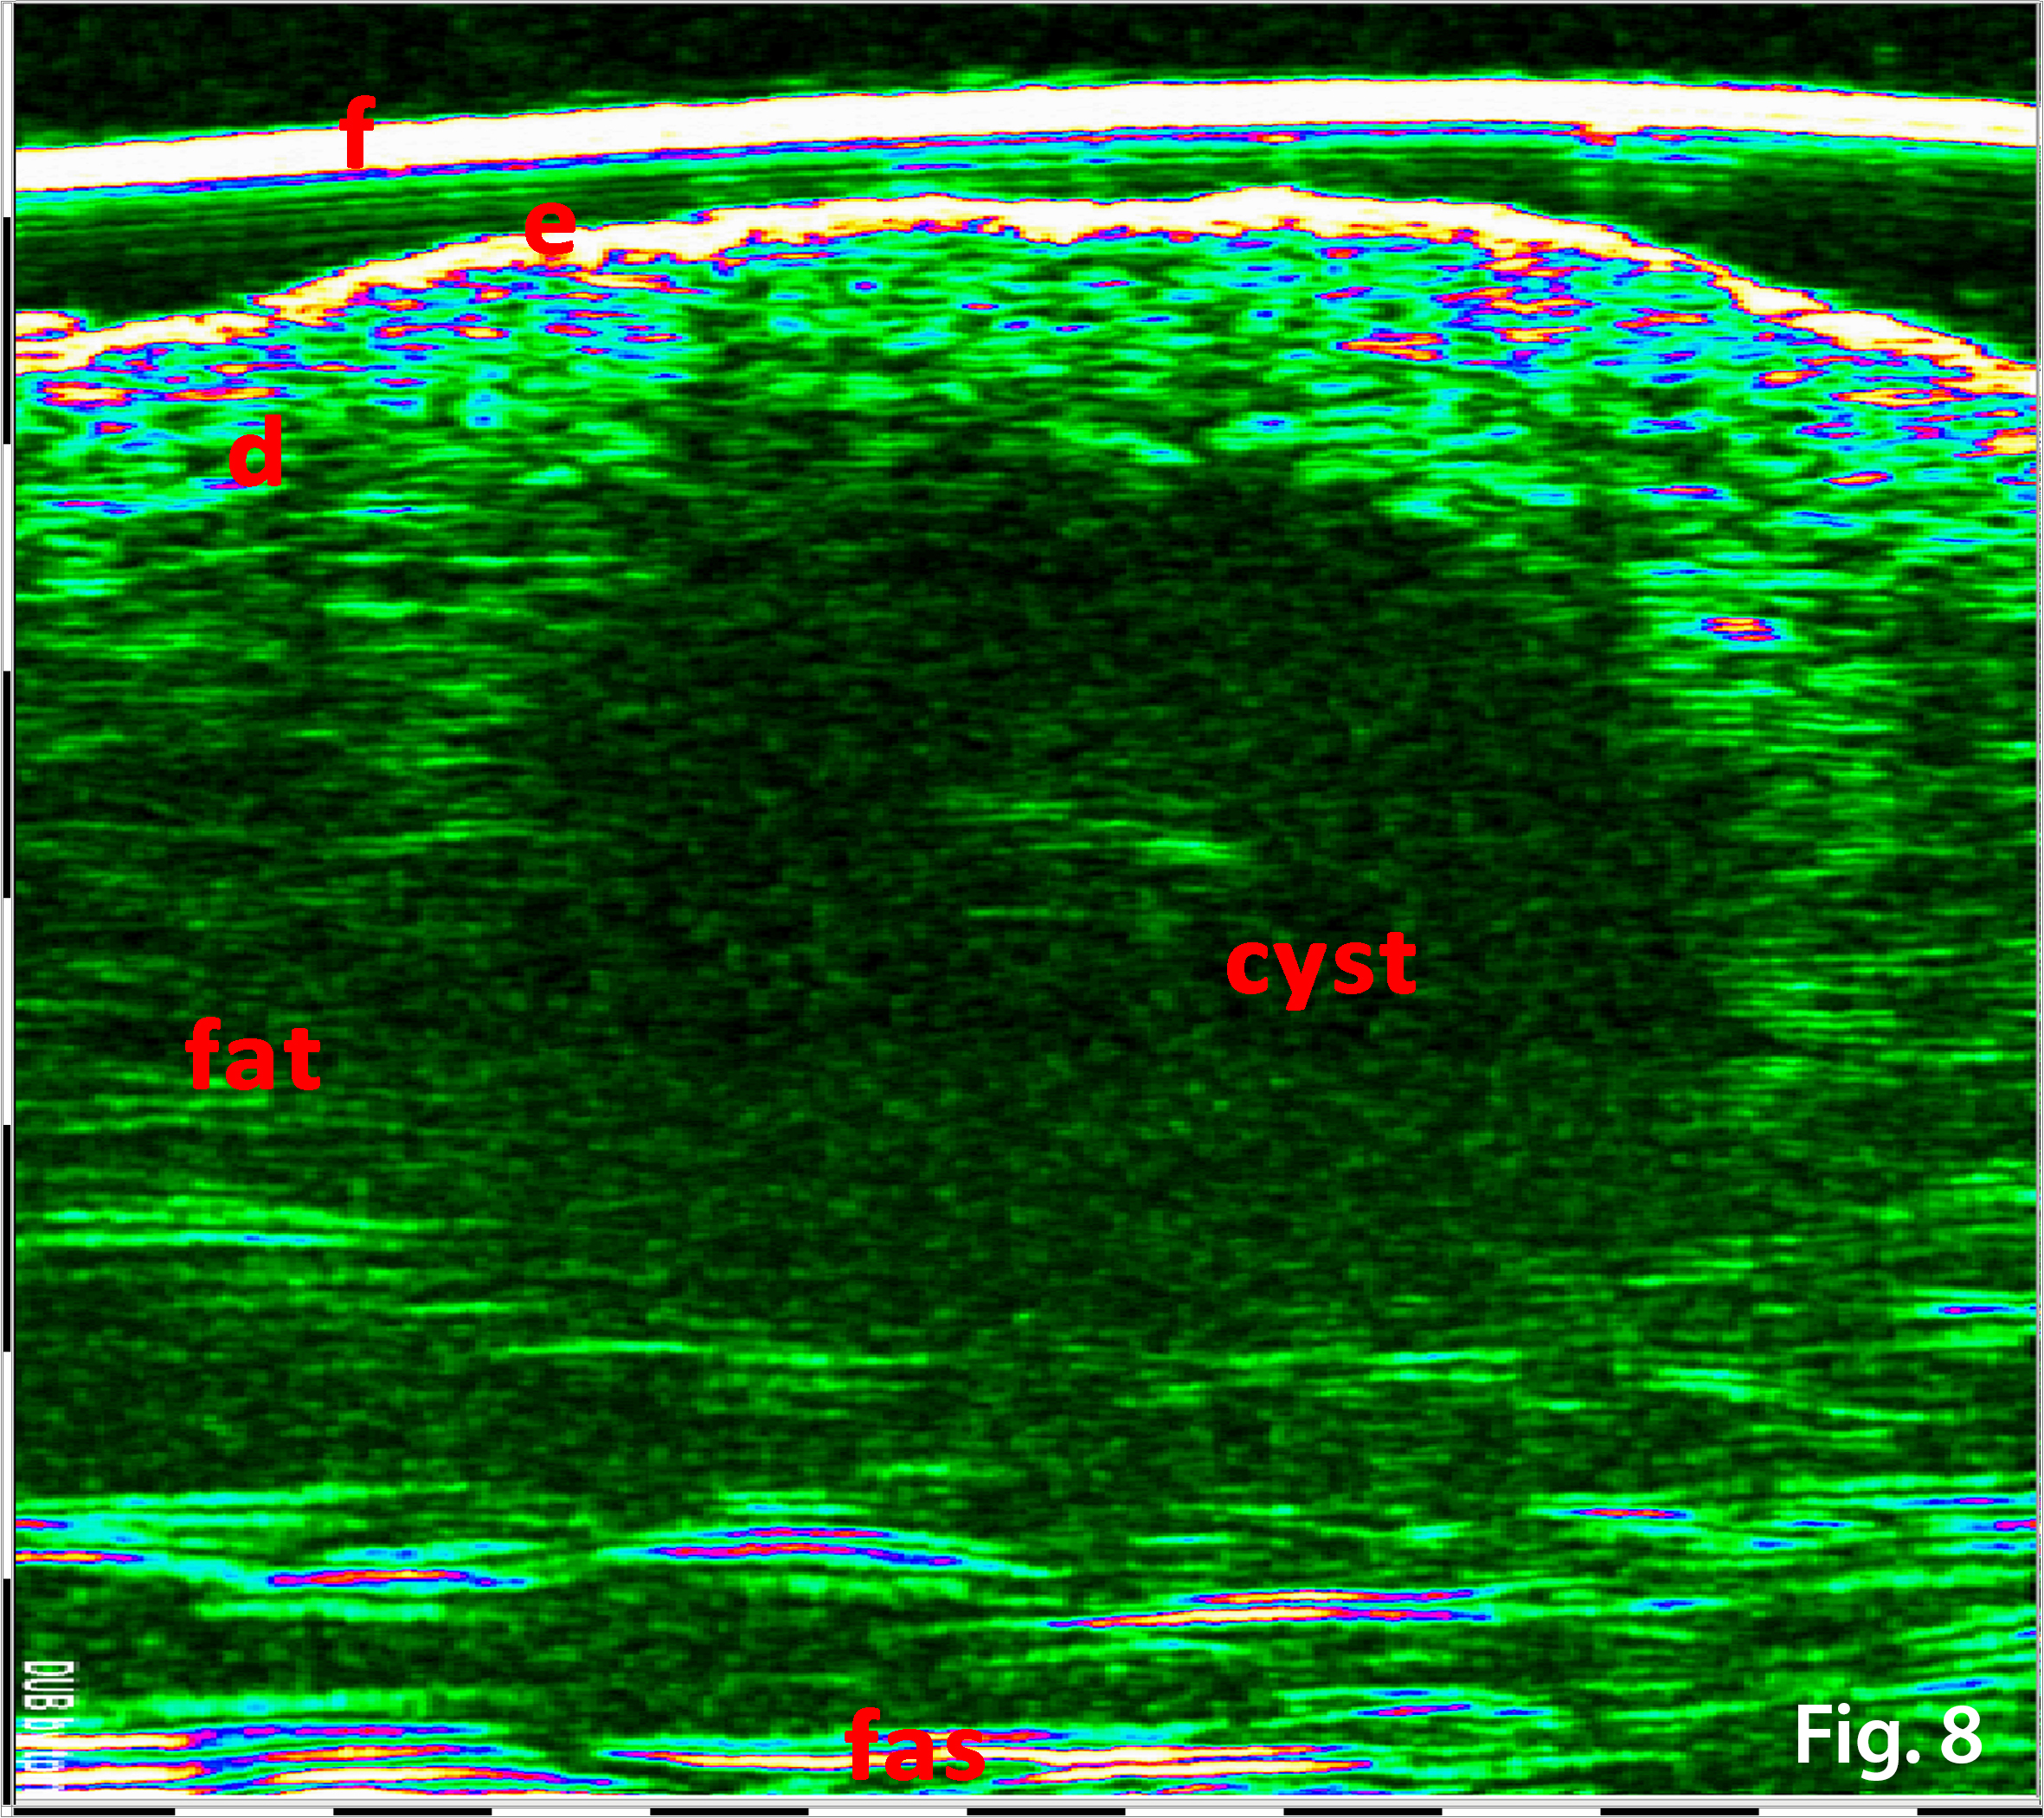

33 MHz ultrasound examination of the adjacent pigmented skin area on the left side of the melanocytic lesion (Fig. 7, Fig 8) revealed a hypo-heteroechoic area 8.2 x 4.2 mm, located in the lower part of the dermis and in subcutaneous fat. The upper margin from the skin surface was 1.26 mm, and a lower margin of 5.2 mm.

The lesion has clear borders and the central portion of the lesion was more hyperechoic than the periphery.

Figure 7. 33 MHz image of the adjacent to the nevus pigmented skin area. f-foil on the tip of the probe, e-epidermis, d-dermis, fat- fat tissue, cyst – dermal cystic lesion margins (red dotted line), fas – fascia. The hypo-heteroechoic area 8.2x4.2 mm is shown located in the lower part of the dermis and within subcutaneous fat. The upper margin from the skin surface 1.26 mm, lower margin 5.2 mm. The lesion has clear borders and a central hyperechoic region.

Figure 8. Same as Fig 7, 33 MHz image of the adjacent to pigmented naevus skin area with Hilbert transformation. The margins of the cyst is better visualized. f-foil on the tip of the probe, e-epidermis, d-dermis, fat- fat tissue, cyst – dermal cystic lesion, fas – fascia.